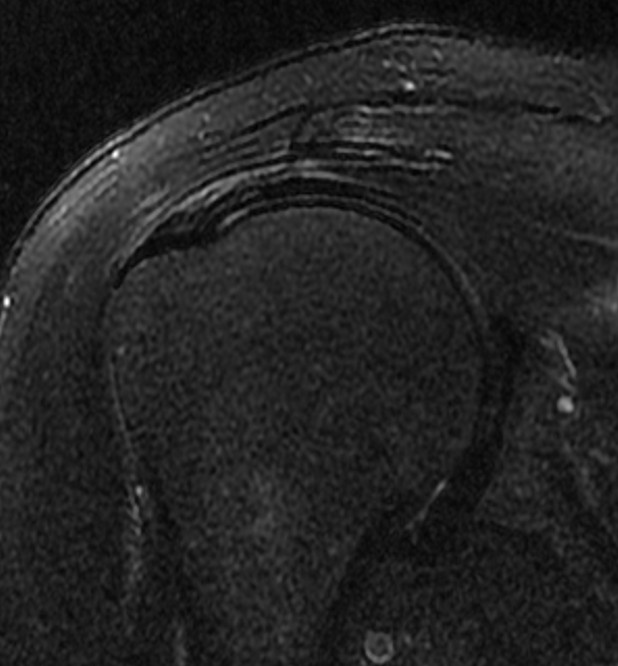

수개월간 지속되는 우측 어깨통증으로 가까운 병원에 내원해서 엑스레이,초음파 검사상 회전근개 부분파열, 염증, 석회로 진단받고 꾸준한 보존적 치료를 시행함. 재생주사치료,충격파치료,도수치료를 꾸준히 시행하였으나 증상이 호전되지 않고, 치료시에만 잠깐 괜찮다가 다시 아프기를 반복. 점차 팔을 조금만 움직여도 통증이 심해지며, 특히 팔을 옆으로 들때나 뻗을때 뒤롤 돌릴때 통증이 심해지고, 밤에도 통증이 시작됨. 시술전(pre) MRI 검사상 회전근개 내측에 부분파열이 관찰되며, 힘줄염이 동반된 상태로 힘줄이 헤지고, 약해진 상태로 진단받고 더핌스 축소봉합술을 시행함. 시술후(post) 시행한 검사에서 약해졌던 힘줄이 정상힘줄로 회복된것이 확인되며, 시술후 바로 일상생활로 복귀하였으며, 어깨를 움직일때 아프던 통증과 야간통이 사라짐